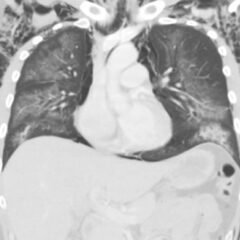

Infant tuberculosis (TB) is a rare but potentially deadly infection and difficult to diagnose, especially in infants who may present with non-specific symptoms. Here, we report a case of an United States-born term infant with community-acquired miliary TB and no confirmed TB exposure history. The patient initially presented with respiratory distress at seven weeks of life with chest radiograph showing a right lower lobe (RLL) infiltrate. After failing multiple courses of treatment for community-acquired pneumonia and developing growth faltering, the patient had imaging findings suggestive of TB infection with CNS involvement. The diagnosis of TB was confirmed by QuantiFERON and purified protein derivative (PPD). In infants who fail conventional treatment for bacterial pneumonia, the differential should be broadened to consider alternative etiologies. Additionally, brain imaging should be performed in cases of disseminated TB despite negative cerebrospinal fluid (CSF) studies since these patients are at high risk of central nervous system (CNS) involvement.